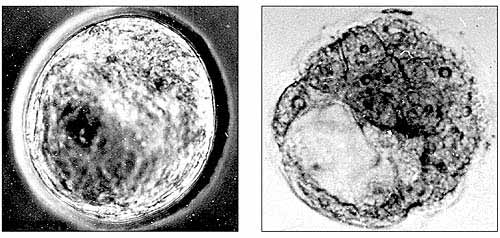

В сериях наших экспериментов со снижением концентрации серотонина в разные критические сроки внутриутробного развития нам удалось подтвердить выявленные П.Г. Светловым общие закономерности реакций эмбриональных тканей на воздействия повреждающих факторов. Блокада парахлорфенилаланином (ПХФА) ключевого фермента синтеза серотонина - триптофангидроксилазы - в доимплантационный период (до внедрения зародыша в стенку матки) часто приводит к торможению вплоть до полной остановки процессов развития зародышей. Нарушается процесс формирования структур, обеспечивающих питание их элементов, в том числе внутренней клеточной массы, дающей начало всем клеткам и тканям эмбрионов (рис.2).

Рис.2. Эмбрионы мыши на четвертый день развития: контроль (слева) - нормально развитый зародыш; опыт (справа) - зародыш с патологиями, вызванными введением ПХФА на второй день беременности самок. Видны полость (бластоцель) и очень крупные по сравнению с контролем клетки трофобласта (наружного клеточного слоя).